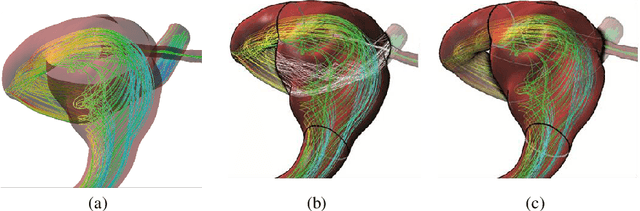

Abstract:An accurate assessment of the cardiovascular system and prediction of cardiovascular diseases (CVDs) are crucial. Measured cardiac blood flow data provide insights about patient-specific hemodynamics, where many specialized techniques have been developed for the visual exploration of such data sets to better understand the influence of morphological and hemodynamic conditions on CVDs. However, there is a lack of machine learning approaches techniques that allow a feature-based classification of heart-healthy people and patients with CVDs.In this work, we investigate the potential of morphological and hemodynamic characteristics, extracted from measured blood flow data in the aorta, for the classification of heart-healthy volunteers and patients with bicuspid aortic valve (BAV). Furthermore, we research if there are characteristic features to classify male and female as well as younger and older heart-healthy volunteers. We propose a data analysis pipeline for the classification of the cardiac status, encompassing feature selection, model training and hyperparameter tuning. In our experiments, we use several feature selection methods and classification algorithms to train separate models for the healthy subgroups and BAV patients. We report on classification performance and investigate the predictive power of morphological and hemodynamic features with regard to the classification oft he defined groups. Finally, we identify the key features for the best models.

Abstract:Morphology of cardiovascular tissue is influenced by the unsteady behavior of the blood flow and vice versa. Therefore, the pathogenesis of several cardiovascular diseases is directly affected by the blood-flow dynamics. Understanding flow behavior is of vital importance to understand the cardiovascular system and potentially harbors a considerable value for both diagnosis and risk assessment. The analysis of hemodynamic characteristics involves qualitative and quantitative inspection of the blood-flow field. Visualization plays an important role in the qualitative exploration, as well as the definition of relevant quantitative measures and its validation. There are two main approaches to obtain information about the blood flow: simulation by computational fluid dynamics, and in-vivo measurements. Although research on blood flow simulation has been performed for decades, many open problems remain concerning accuracy and patient-specific solutions. Possibilities for real measurement of blood flow have recently increased considerably by new developments in magnetic resonance imaging which enable the acquisition of 3D quantitative measurements of blood-flow velocity fields. This chapter presents the visualization challenges for both simulation and real measurements of unsteady blood-flow fields.